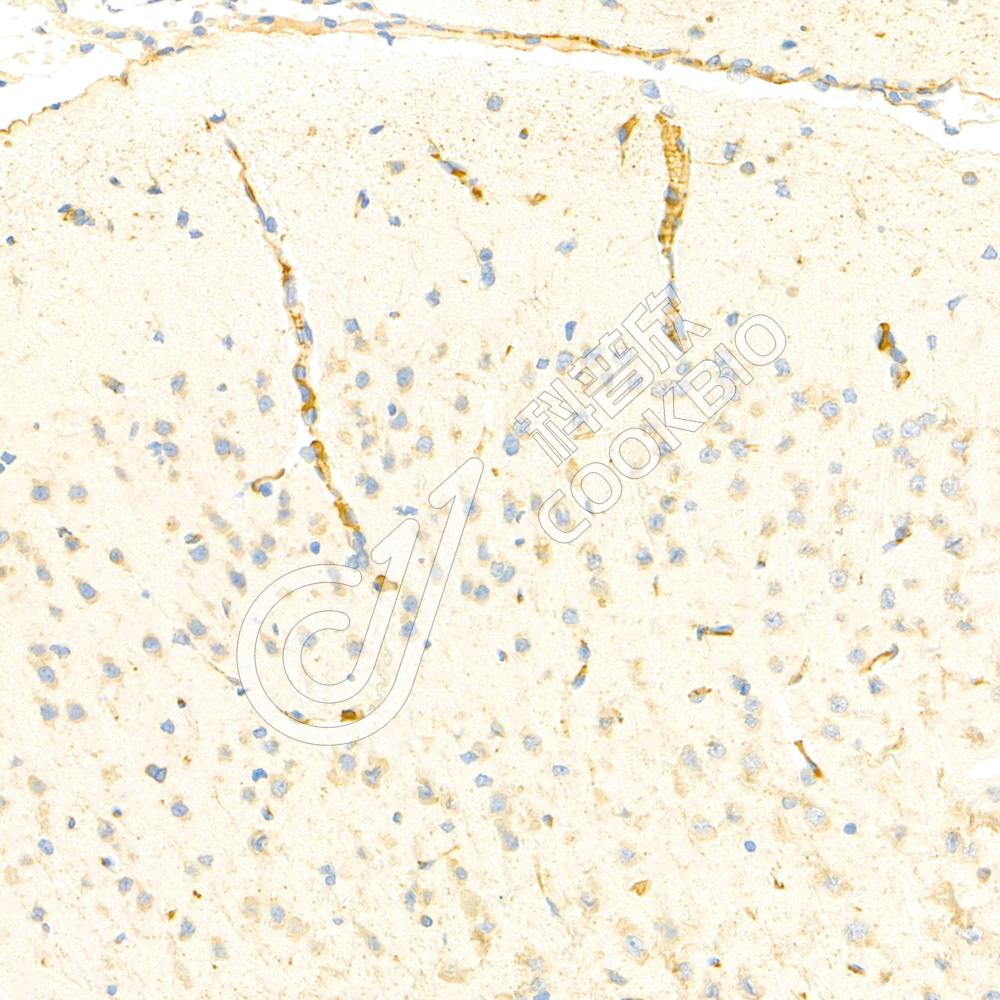

IHC检测Synphilin 1蛋白(货号 K1335973).

样品: 大鼠脑, 4%多聚甲醛 (货号KSG1101) 固定12-24小时.

抗原修复: Tris-EDTA抗原修复液(pH 9.0) (KSG1203), 98℃, 20分钟.

—抗: 1: 1200稀释, 4℃ 孵育过夜.

二抗: S-vision免疫组化多聚二抗(山羊抗兔),即用型 (货号KB3906), 室温孵育20分钟.